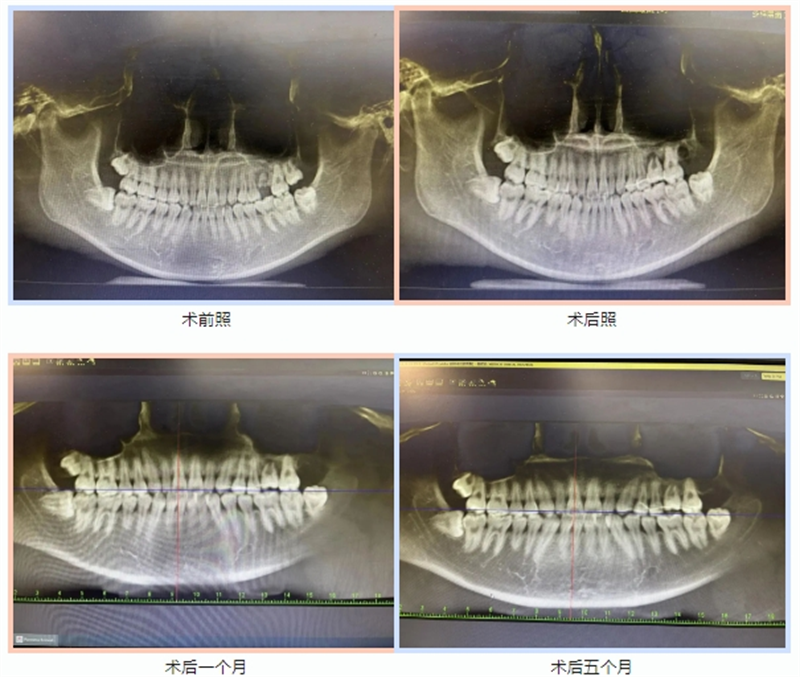

李长顺和胥加斌医生对其进行了详细的临床检查和锥形束数字断层影像检查(CBCT),发现患者左上智齿萌出性齦炎、左上第一磨牙龋坏残根。以往临床上都将这类智齿视作“废物”,会建议患者及时拔除。但该智齿大小与即将拔除的残冠相仿,利用临床较为成熟的自体牙移植技术就能实现“移花接木”,完成拔除残冠的即刻修复。

据了解,在为患者进行智齿牙移植时采用CBCT联合3D打印技术,术前通过数字化技术辅助设计治疗方案制定严密的手术方案,减少了手术创伤、降低手术难度、缩短手术时间,提高自体牙成功率。2024年1月,患者复诊拍摄CBCT,检查后患者的牙齿长得很牢固,自体牙移植治疗已经获得成功,预期随着牙槽骨进一步愈合,牙周膜间隙将会呈现出来。移植过来的智齿,在新的牙位上,很快就能适应。